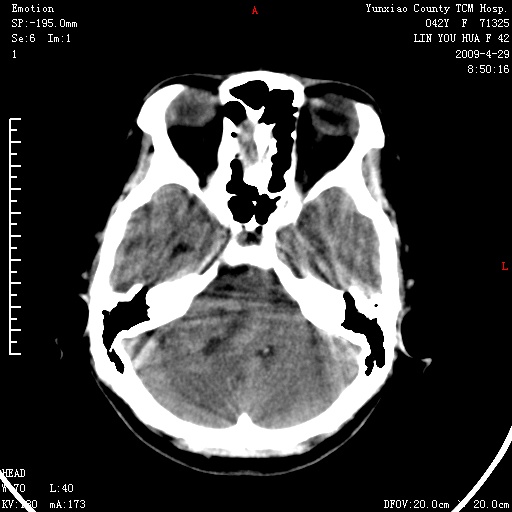

右侧桥小脑角区肿瘤,高密度囊变有显著强化,骨窗见内听道显著扩大,考虑听神经瘤可能性大

1)右侧听神经瘤。2)阻塞性脑积水。

内听道扩大,支持考虑听神经瘤可能性大。